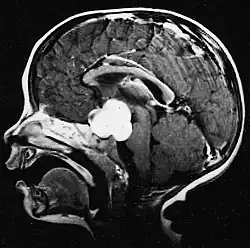

Stereotactic MRI brain scan showing a recurrent postoperative brain stem cystic pilocytic astrocytoma.

Sagittal T1-weighted MRI showing a well-circumscribed hypointense mass in the tectum (presumably a tectal plate glioma). These lesions are a distinct subset of pilocytic astrocytoma which present with hydrocephalus typically in 6 to 10 year-olds and are rarely progressive lesions. When imaging is characteristic, a biopsy is usually not performed because of the risks to adjacent structures, often shunting to relieve intracranial pressure is the only treatment required.